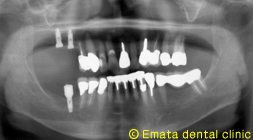

上の奥歯が欠損したが骨がないのでインプラント治療はあきらめていた 68歳女性(上顎洞挙上術【ソケットリフト】の治療例)

右上の歯が欠損しインプラント治療を希望されました。

奥歯の上には上顎洞という空洞(黄色の線)がありこのままではインプラントが上顎洞内に突き抜けてしまうためインプラントの手術ができません。

上顎洞挙上術(ソケットリフト)をおこないインプラントを埋入しました。

上顎洞の位置が低いためにインプラントが困難な方にもこの手術を併用することでインプラントが可能となります。